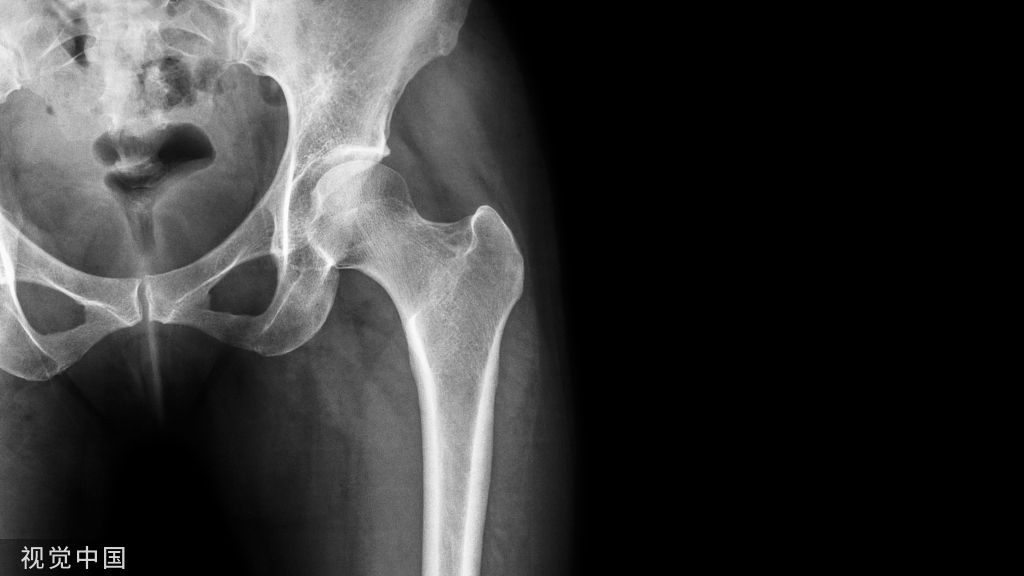

按部位分的话,主要有三种近端、断端、远端:

1.近端是最常见的,大部分的并发症都集中在了近端,主要是导致了切出、穿凿、内翻、退钉等。

头钉过短、内侧支撑不足、导致的6周出现内翻,最后肢体短缩2cm,出现这些的原因,意味着骨折不稳定!初始固定没有达到应该稳定骨折的效果